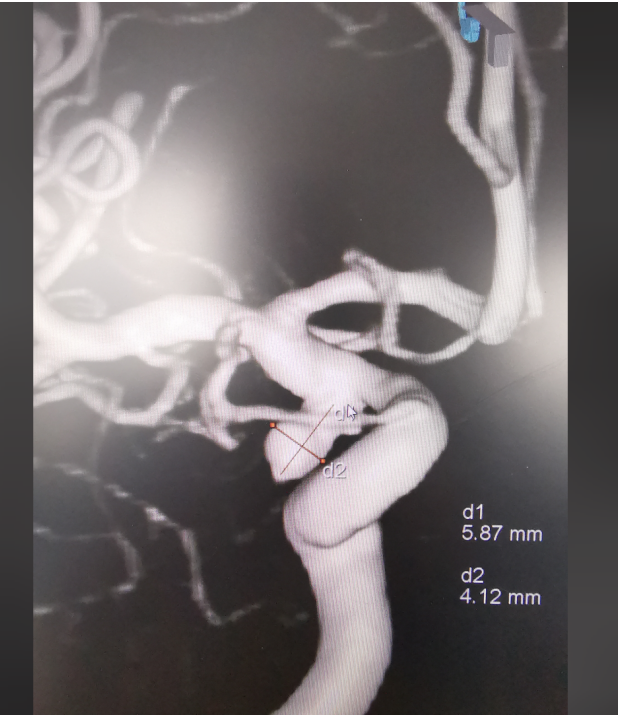

神经外科会诊后,高度怀疑颅内动脉瘤破裂出血,最终经CT血管造影检查(CTA),确诊患者为右侧后交通动脉瘤。

CTA影像